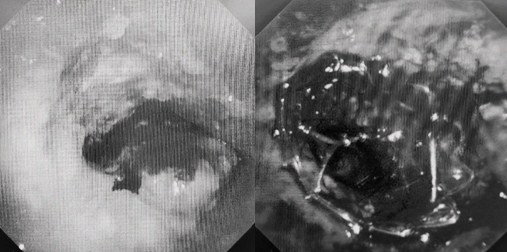

時間就是生命!了解患者病情后,歐陽海峰立刻啟動氣道梗阻緊急救治通道,協(xié)調(diào)院前轉(zhuǎn)運,急診快速入院流程。凌晨患者入院胸部CT顯示,現(xiàn)存唯一的呼吸通道在右主支氣管處,狹窄處僅約3毫米,患者命懸一線!

運用呼吸介入技術(shù),軟硬鏡結(jié)合快速開通氣道,是患者目前唯一可行的治療方案,手術(shù)刻不容緩!但存在麻醉后氣道完全塌陷閉合、大出血、窒息等巨大風險?;颊叽饲敖舆B轉(zhuǎn)診3家醫(yī)院,均建議保守支持治療或轉(zhuǎn)院。歐陽海峰詳細了解患者病史,全面評估影像檢查結(jié)果后,決定盡快進行手術(shù),組織醫(yī)護團隊對患者進行持續(xù)密切監(jiān)測,充分保障其術(shù)前安全。

患者入院第二天,在麻醉手術(shù)中心全力配合下,歐陽海峰帶領(lǐng)呼吸介入團隊,歷時40分鐘快速置入硬質(zhì)支氣管鏡、鏟切腫瘤,并順利植入全覆膜TTS支氣管金屬支架。患者氣短癥狀即刻緩解,為患者贏得了寶貴的后續(xù)治療機會。